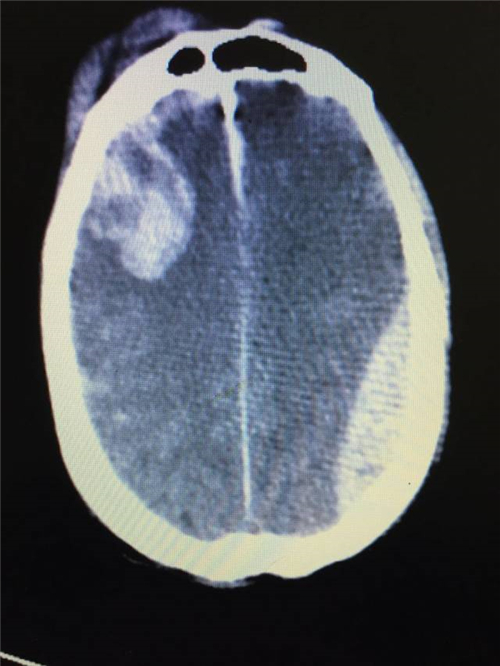

最近,我科成功抢救了一名生命垂危的高龄脑外伤患者。患者系汝城县人,因高处坠落后导致昏迷、颅内出血,被立即送入汝城县中医院进行救治,当地医院紧急处置后因技术及设备无法满足进一步救治要求,遂与我科联系后进行紧急转院。

从患者到达我院再到开始手术仅仅花费40分钟,这为患者的进一步救治赢得了宝贵的时间。紧接着由我带领几名神经外科骨干,经过近2小时的手术,成功清除了患者颅内血肿。但此时患者肺部呼吸功能严重障碍,我们考虑患者颅底骨折发生误吸,导致气道不畅,立即请ICU会诊,ICU赵阳医生立即予以纤支镜下清理呼吸道异物,经过一个多小时的努力终于将双肺内气道异物清洗干净,恢复了患者的肺功能。

术前